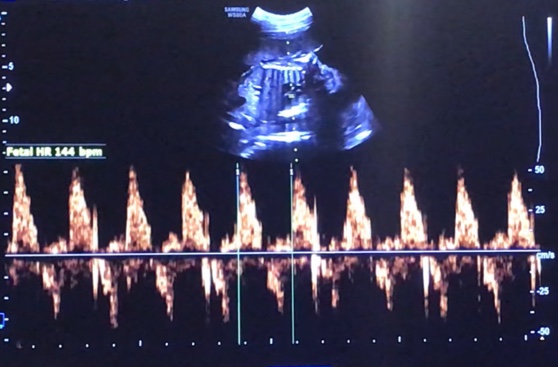

보통 이전의 주차에서는 머리~엉덩이까지 길이를 항상 재주셨는데 이번 진료에서는 복부둘레를 확인하신 후에 복건이가 약 700~750g 정도 된다고 말씀해 주셨다. 복부 둘레는 19.75cm, 심장박동수는 144 bpm.